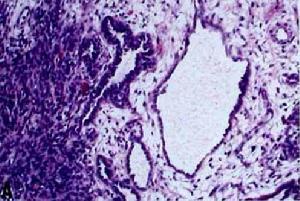

Sertoli-Leydig細胞瘤4 網狀型Sertoli-Leydig細胞腫瘤。在細胞性結節的周邊,網狀型空隙周圍是水腫的卵巢間質